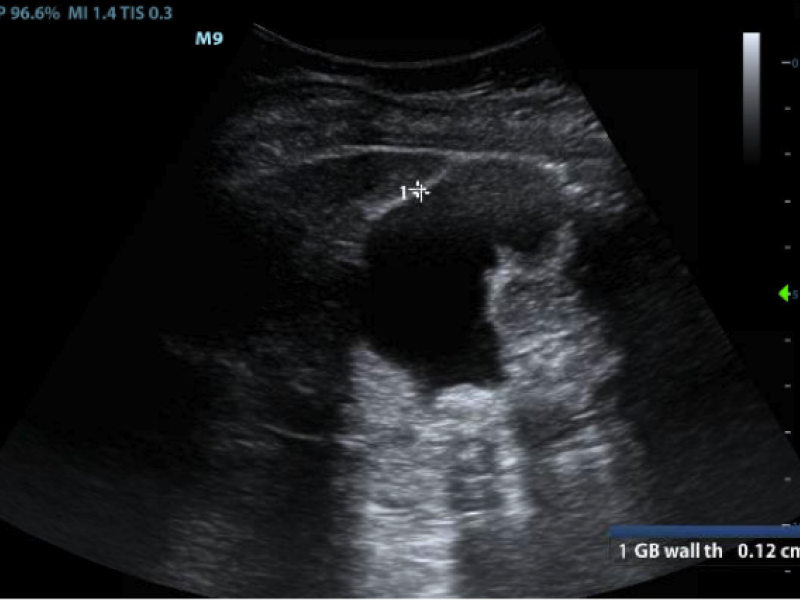

Answer : 5. Number of gallstones. 1, 2, 3, and 4 (also known

EM Daily

Imaging Case Answer: Cholecystitis vs Cholelithiasis

August 30 2016